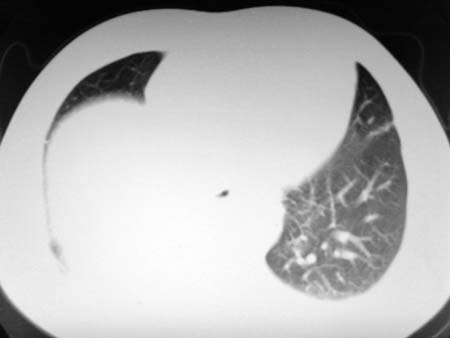

以下是引用qian在2008-4-27 17:02:00的发言:[br]考虑右下肺肺段隔离症伴有感染,建议做增强看看。

以下是引用zsl6918在2008-4-27 17:13:00的发言:[br]考虑右肺下叶炎性病变可能性大,建议抗炎治疗后复查,现有资料不能完全除外肺癌可能。